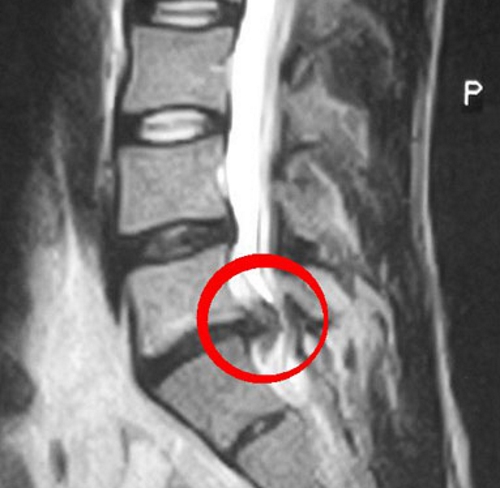

Диагностические меры

Диагностика межпозвоночной грыжи в поясничной области — важный этап выбора метода лечения. Врач сначала собирает информацию о состоянии пациента и проводит первичный осмотр. Необходимо выяснить симптомы, указывающие на сжатие нервных корешков.

Ключевыми процедурами для точного диагноза являются:

- МРТ (магнитно-резонансная томография). Этот метод использует безопасное магнитное поле и позволяет получить высококачественные изображения внутренних органов. МРТ помогает определить местоположение грыжи и назначается при подозрении на грыжу в крестцовом отделе позвоночника.

- КТ (компьютерная томография) эффективно визуализирует состояние костных структур, используя рентгеновское излучение для получения изображений.

- Рентгенография применяется для подтверждения ранее установленных диагнозов.

При необходимости могут быть назначены и другие методы диагностики в зависимости от состояния здоровья пациента и проявляющихся симптомов.